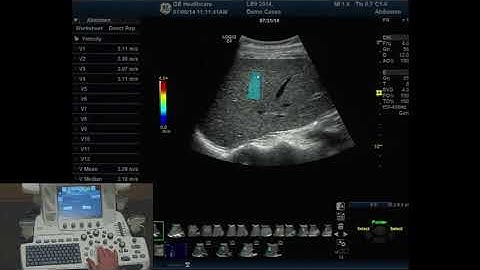

How to Perform VShear & Point VShear | Shear-Wave Elastography Tutorial